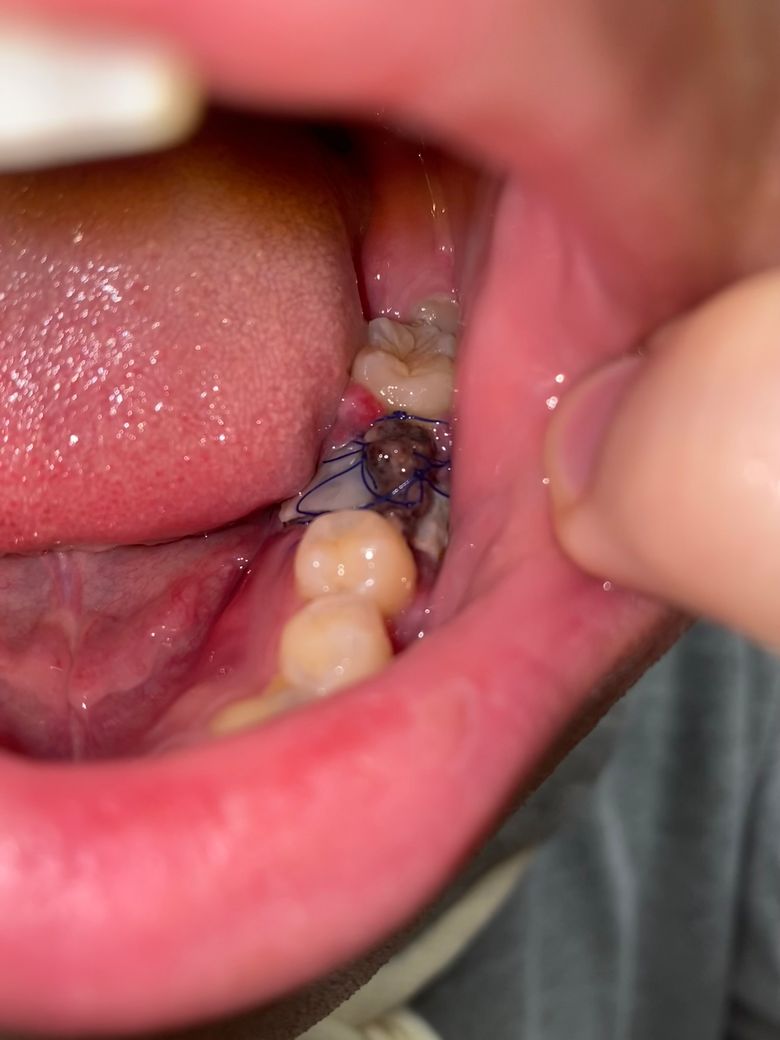

치과측에서는 2주 이후로 예약을 잡은 상태인데요. 사진에 보다싶이 실밥이 거의다 풀어져 밥을 먹을때 실을 건들거나 움직여 불편함이 있는 상황입니다. 고정된 옛 잇몸? 들도 따 떨어져 실밥의 역할이 다 한건 아닐지 싶네요. 이러한 이유로 내원해서 이러한 이유로 실밥을 제거할 수 있는지 여쭤보면 가능한지 전문가분의 의견을 먼저 듣고싶습니다.

• 1번 째 사진